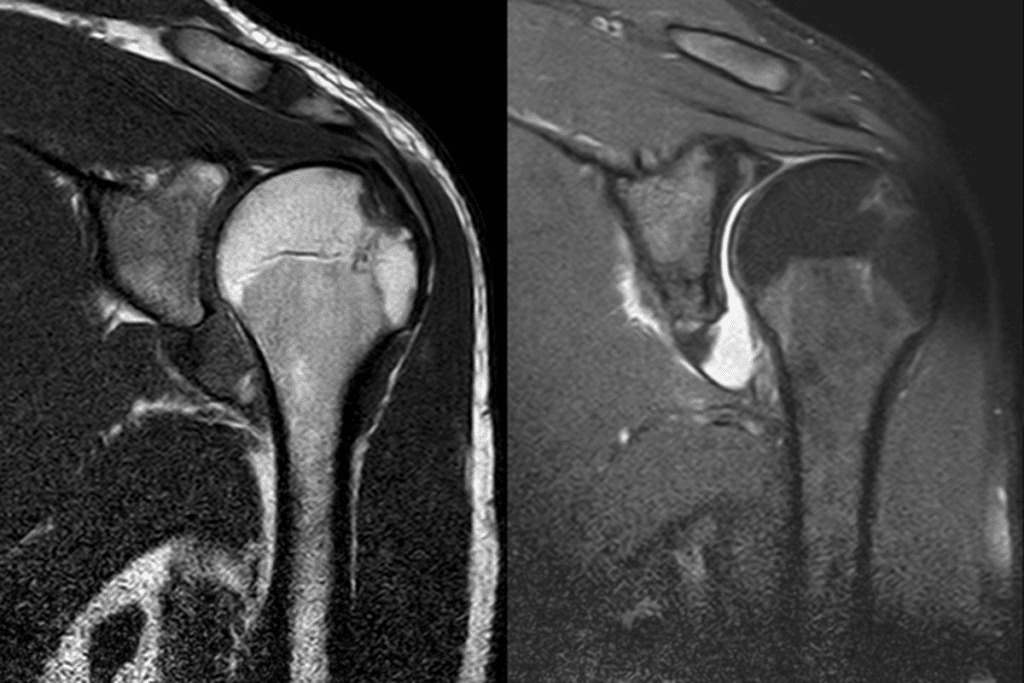

Magnetic resonance imaging (MRI) excels at showing ligament tears or cartilage damage. These details help doctors adjust pain management timelines. For complex cases involving shattered bones, computed tomography (CT) scans provide 3D views that inform surgical planning.

X-rays confirm bone alignment after injury. For soft tissue assessment, MRI scans evaluate ligament tears, while CT scans detect subtle fractures. These tests guide treatment plans for complex cases.